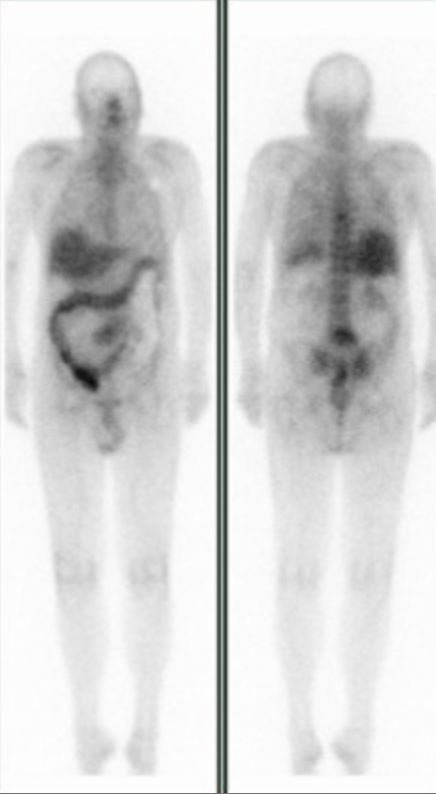

Normal Study

• Normal uptake in

• Liver

• Kidneys early, but if see kidney after 24 hours = bad

• Faint uptake in breasts

• Lacrimal gland uptake

• Some faint GI uptake